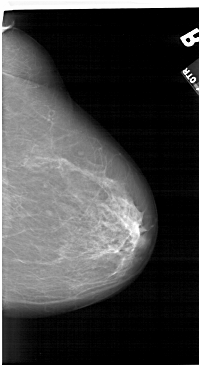

A_1124_1.RIGHT_MLO

RIGHT_MLO LINES 6361 PIXELS_PER_LINE 3751 BITS_PER_PIXEL 12 RESOLUTION 43.5 NON_OVERLAY